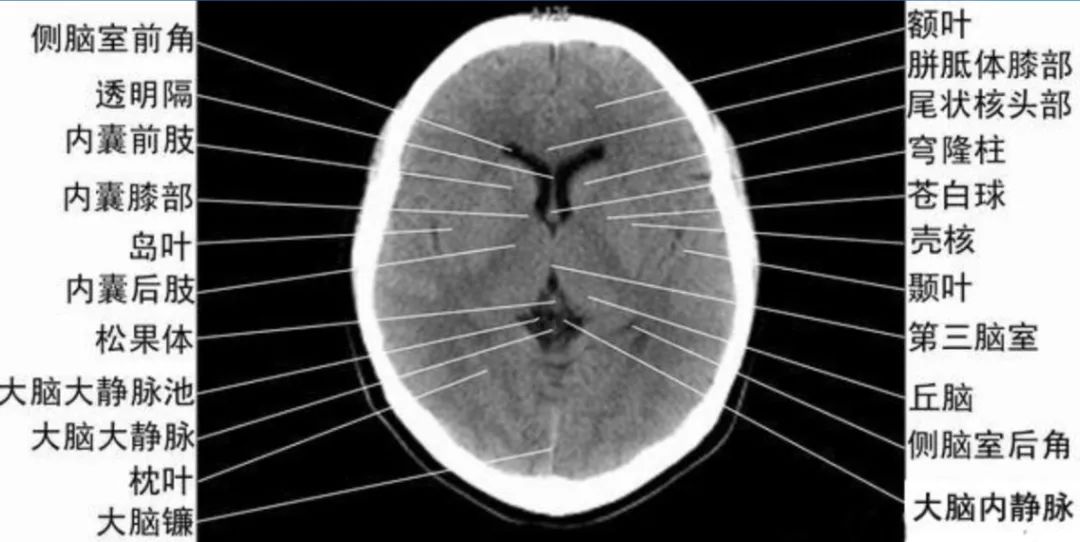

4、第三脑室上部层面基底核、丘脑。

内囊前脚(前肢);尾状核和豆状核之间。

内囊膝部和后脚(后肢):位于豆状核(由外侧的壳核和内侧的苍白球组成)及丘脑之间。

壳核的外侧:外囊、屏状核、最外囊、岛叶(脑岛)。

四叠体池:两侧枕叶之间,池内有松果体,向前与第三脑室连接。

基底节(基底核):埋藏在两侧大脑半球深部的灰质核团,是组成锥体外系的主要结构。

基底节区:概念不清。可能包括:基底节、黑质、红核、及其周围白质区域。

内囊:位于丘脑、尾状核、豆状核之间的白质区,是由上、下行的传导束密集而成。分为三部分:前肢、膝部、后肢。膝部有皮质脑干束;后肢有皮质脊髓束、丘脑皮质束、听辐射和视辐射。

外囊:是位于屏状核和豆状核之间的白质带,主要由岛叶发出的皮质被盖纤维组成。